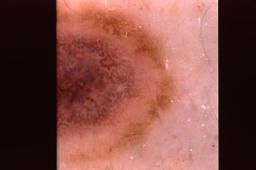

{

"age_approx": 70,

"anatom_site_general": "upper extremity",

"concomitant_biopsy": true,

"dermoscopic_type": "contact non-polarized",

"diagnosis_1": "Benign",

"diagnosis_2": "Benign melanocytic proliferations",

"diagnosis_3": "Nevus",

"diagnosis_4": "Nevus, Combined",

"diagnosis_confirm_type": "histopathology",

"image_type": "dermoscopic",

"lesion_id": "IL_5477327",

"melanocytic": true,

"patient_id": "IP_3514971",

"sex": "female"